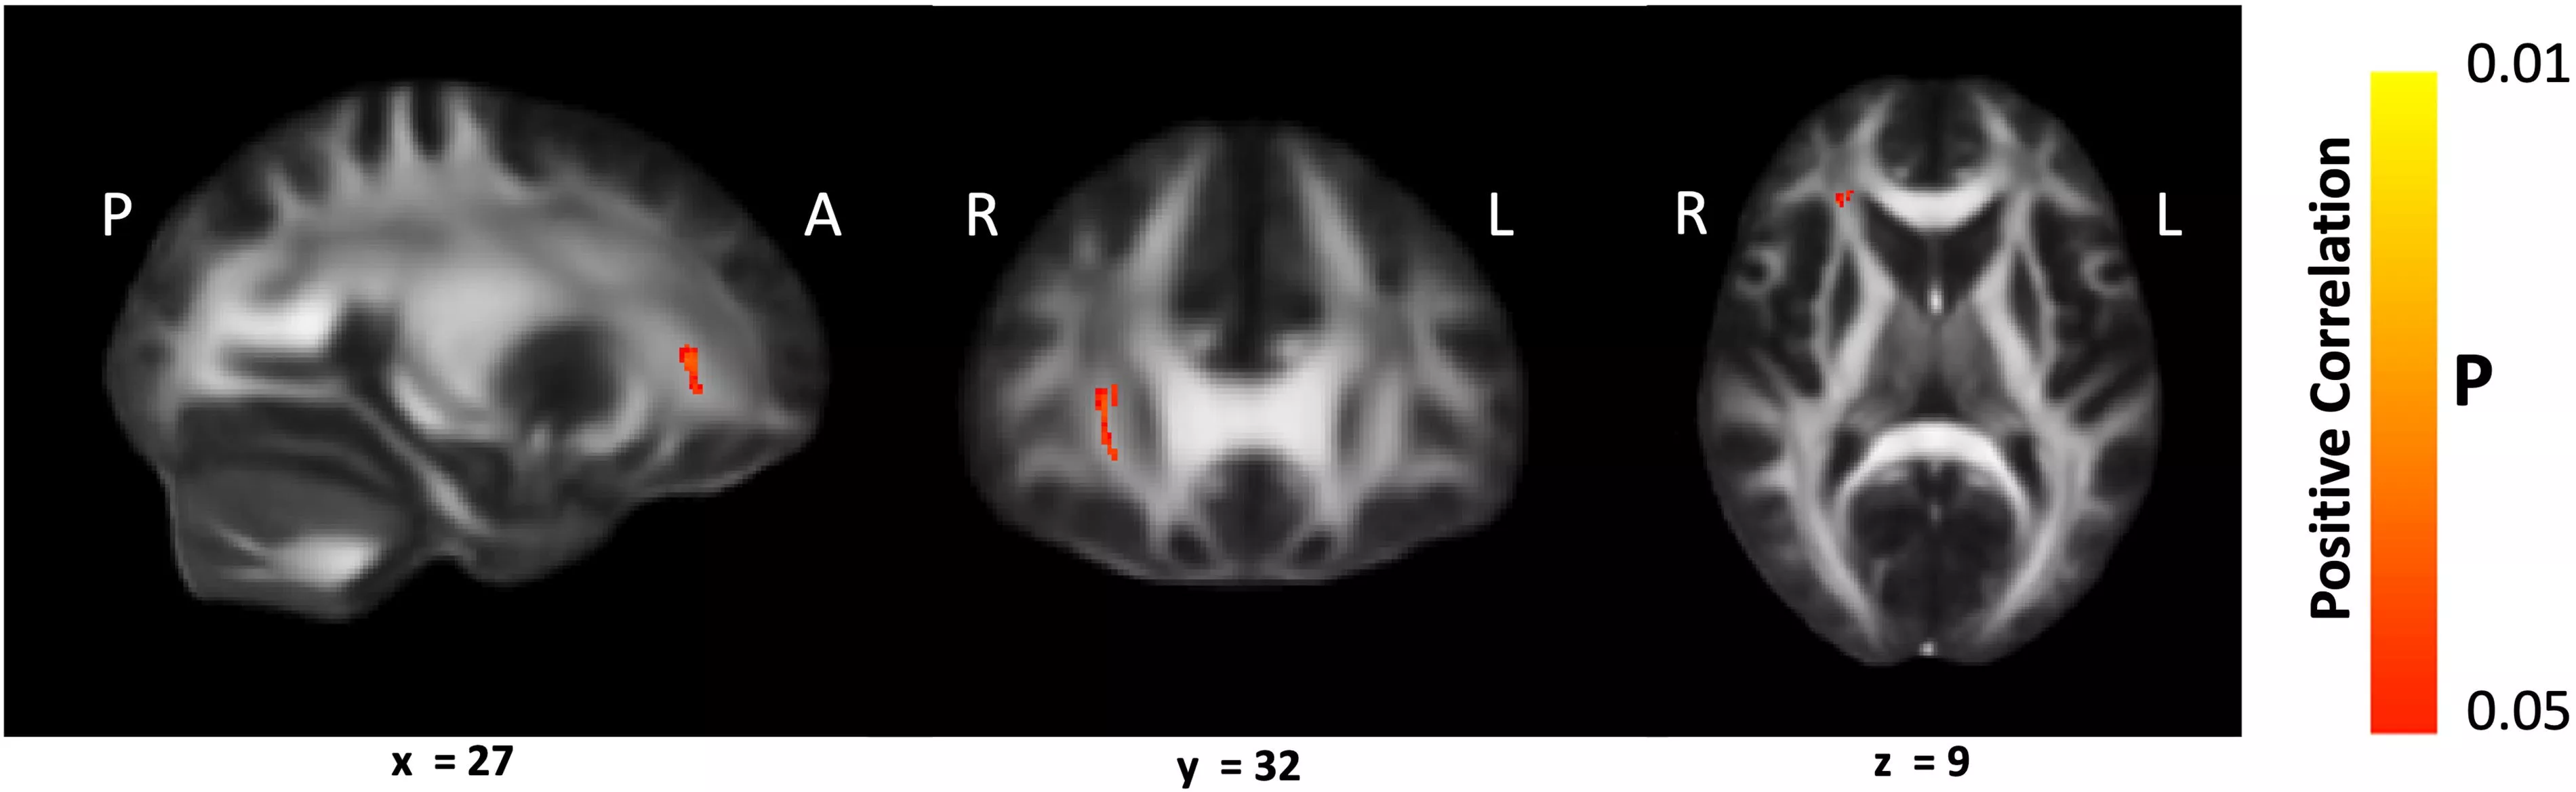

Goal-Oriented Attentional Self-Regulation (GOALS) is a cognitive rehabilitation training program that targets executive control functions in participants by applying mindfulness-based attention regulation and goal management strategies. The study found there was significantly better white matter microstructural integrity in left and right anterior corona radiata (ACR) in the GOALS group compared with the control group. They found a significant correlation between sustained attention ability of GOALS participants and white matter integrity of their right ACR pre- and post-training and that improvement was the result of increased neurite density and decreased fiber orientation dispersion within this tract.

Image

Sagittal, coronal, and axial brain MRI slices with small red highlighted clusters indicating areas of positive correlation. Orientation markers (P, A, R, L) and slice coordinates (x = 27, y = 32, z = 9) are shown. A vertical color bar labeled Positive Correlation displays p values ranging from 0.01 to 0.05.

Tracts with significant correlation between white matter fractional anisotropy (FA) and sustained attention score in Goal-Oriented Attentional Self-Regulation (GOALS) group. (Fig. 2)